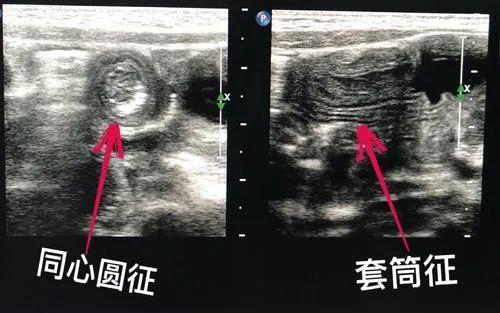

经腹部超声检查发现右下腹部肠管局部呈团块状,其横切面呈“同心圆征”,纵切面呈“套筒征”,这是典型肠套叠的超声表现。根据该检查结果,儿科医生及时予以临床处理,避免了不必要的并发症。

肠套叠是肠管的一部分及其邻近的肠系膜进入邻近扩大的肠腔内所引起的梗阻症状。那么其相应的超声声像图表现包括:套叠部位的肠管横切面表现为高低回声交替的多环状的“同心圆征”或外周低回声圈,中央高回声区表现为“靶环征”,纵切面表现为高低回声交叉的“套筒征”,且结构之间呈现为平行状。一般肠套叠多见于2岁以内患儿,尤其是4-10个月为高峰期。